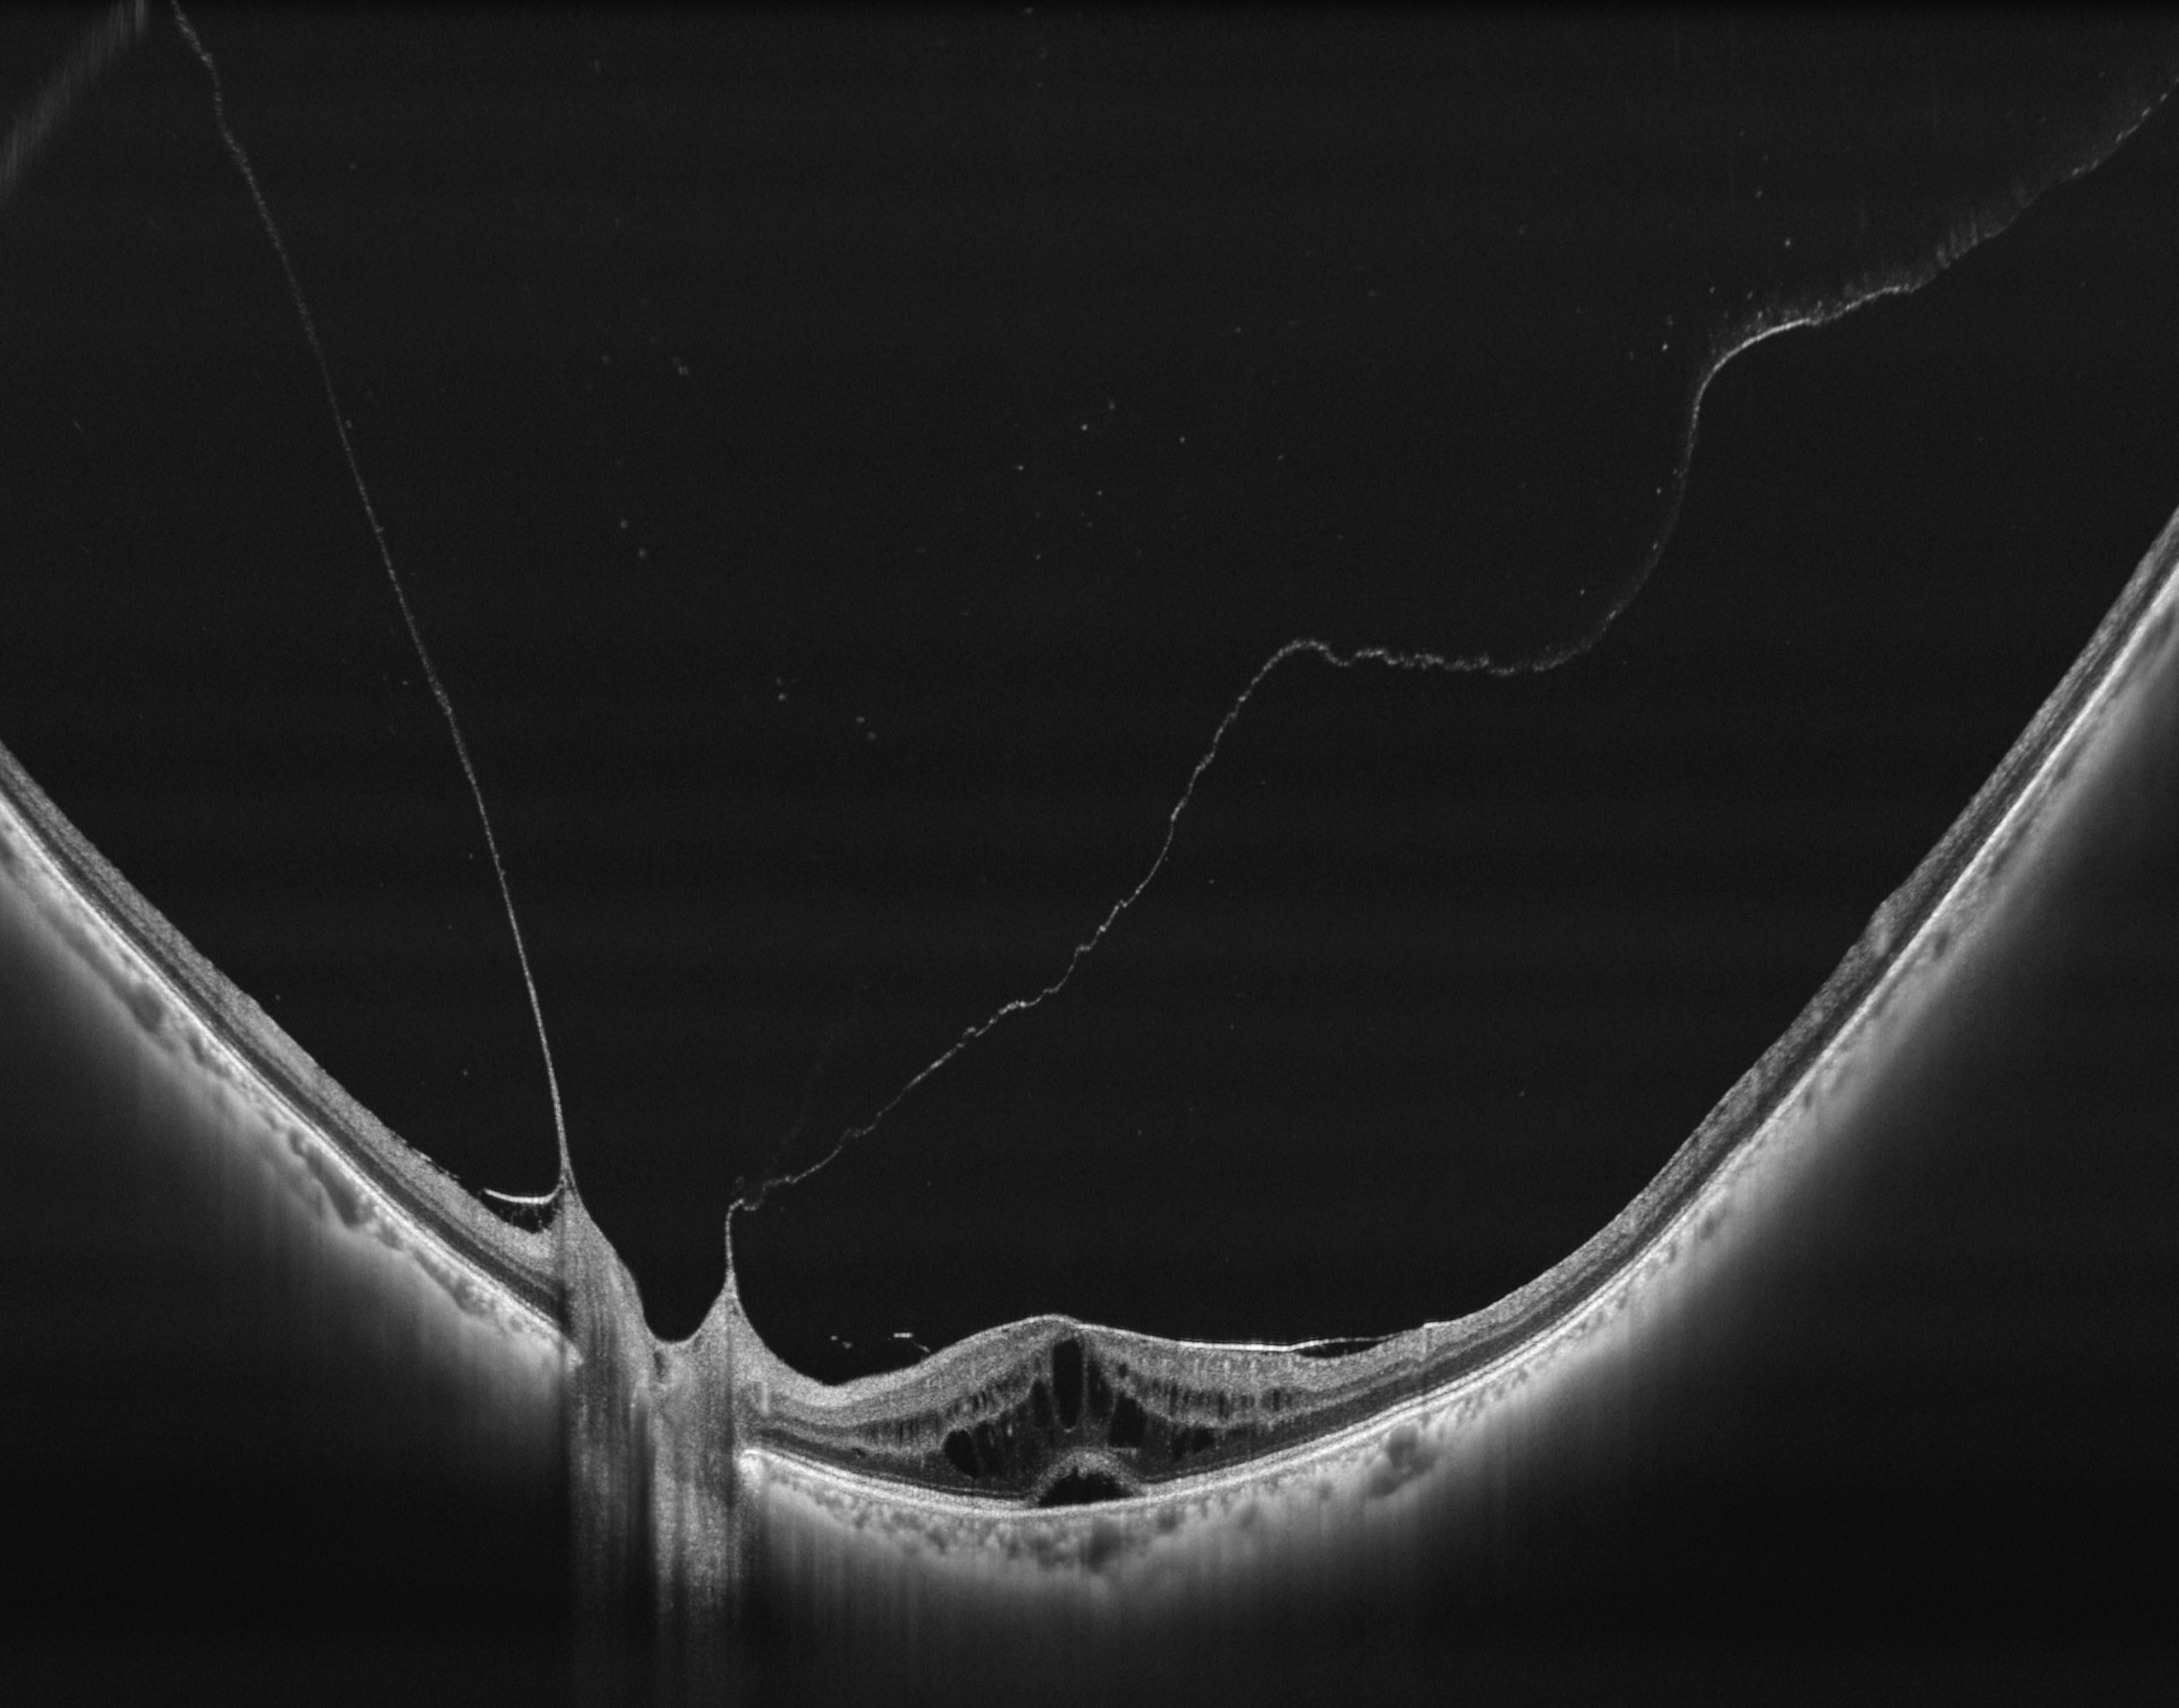

Full Range Retina OCT

- Van achterste glasvocht tot choroidea-sclera

- 24 mm tot 6 mm netvliesscan

- Automatische laagdetectie, segmentatie en meting van elke laag van het netvlies en choroïd

Voorste Oogsegment (AS) OCT

- 18mm X 6mm voorste oogsegment (AS) OCT

- Automatische metingen: CCT, ACD, LT, enz.

- Automatische identificatie van sclera-uitloper en hoekrecessie